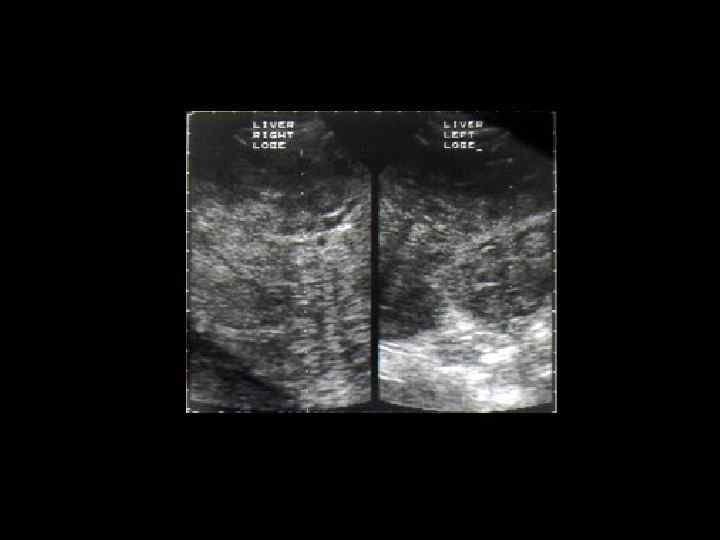

АКТУАЛЬНЫЕ ВОПРОСЫ РЕНТГЕНОЛОГИИ ЛУЧЕВАЯ ДИАГНОСТИКА ОЧАГОВЫХ ПОРАЖЕНИЙ ПЕЧЕНИ КАВЕРНОЗНАЯ ГЕМАНГИОМА Ультразвуковая семиотика: - гиперэхогенное образование округлой или овальной формы - с четкими контурами - однородной структурой